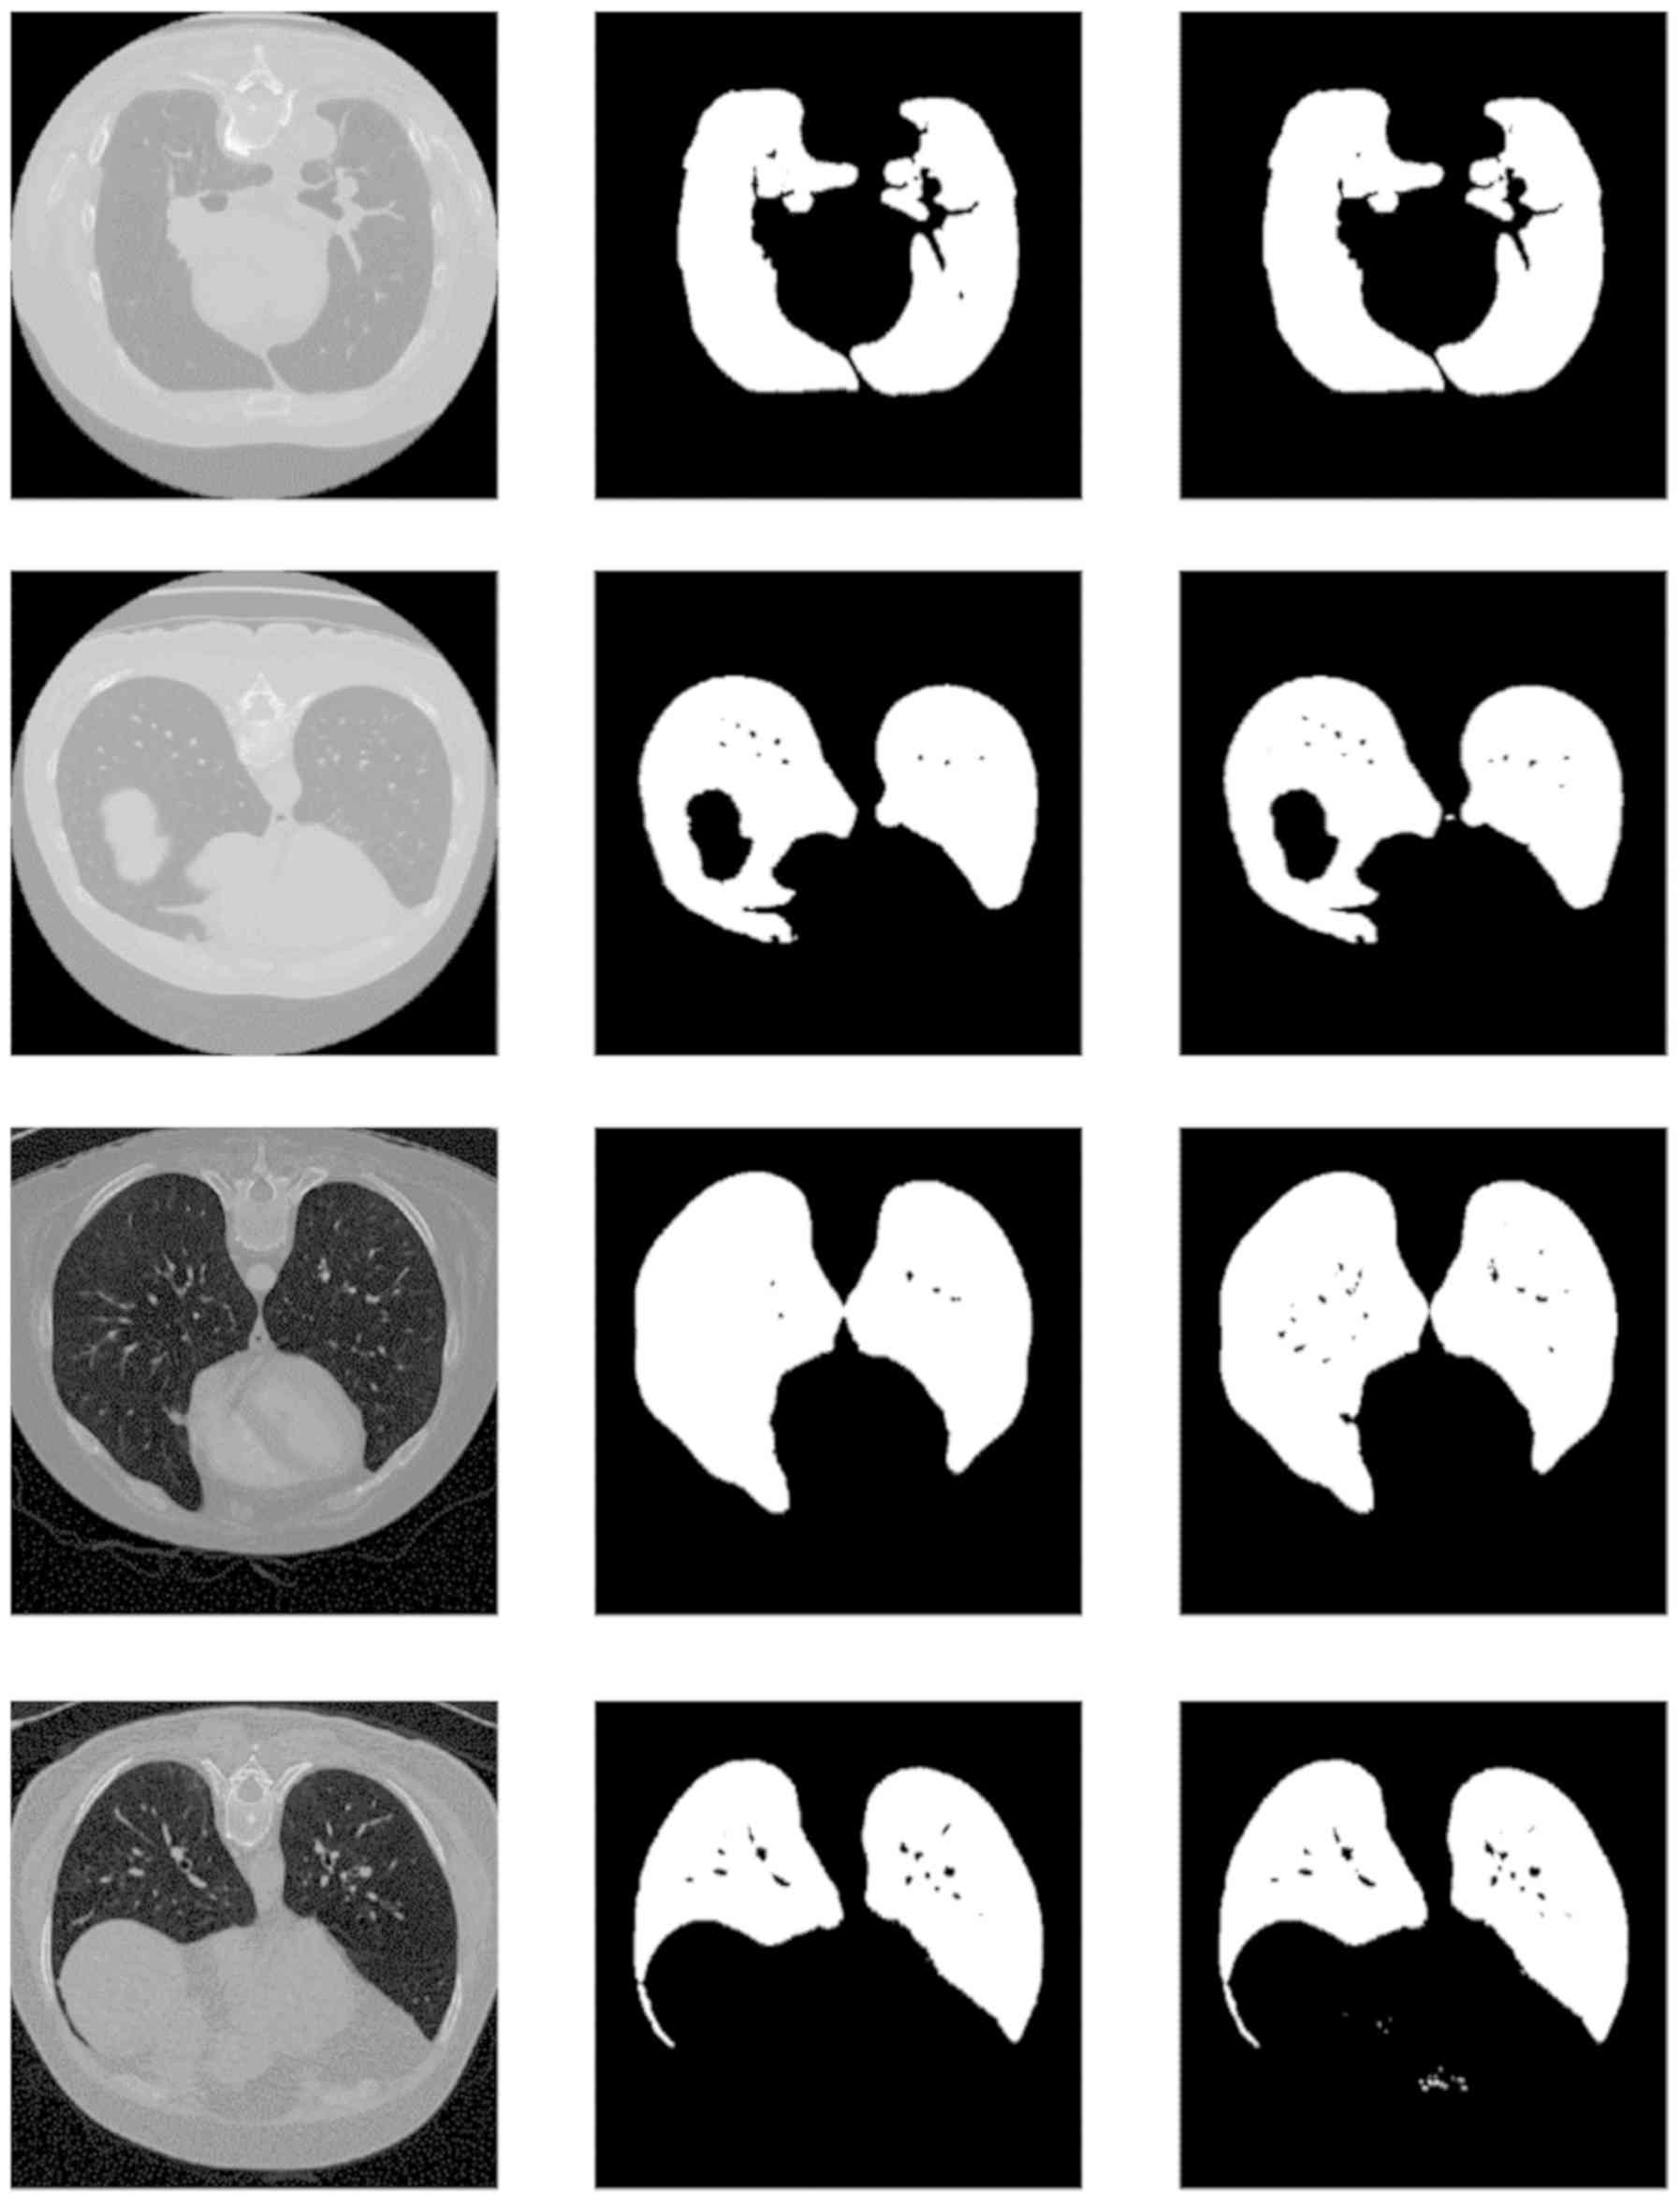

Advancing Covid‑19 differentiation with a robust preprocessing and integration of multi‑institutional open‑repository computer tomography datasets for deep learning analysis

The coronavirus pandemic and its unprecedented consequences globally has spurred the interest of the artificial intelligence research community. A plethora of published studies have investigated the role of imaging such as chest X‑rays and computer tomography in coronavirus disease 2019 (COVID‑19) automated diagnosis. Οpen repositories of medical imaging data can play a significant role by promoting cooperation among institutes in a world‑wide scale. However, they may induce limitations related to variable data quality and intrinsic differences due to the wide variety of scanner vendors and imaging parameters. In this study, a state‑of‑the‑art custom U‑Net model is presented with a dice similarity coefficient performance of 99.6% along with a transfer learning VGG‑19 based model for COVID‑19 versus pneumonia differentiation exhibiting an area under curve of 96.1%. The above was significantly improved over the baseline model trained with no segmentation in selected tomographic slices of the same dataset. The presented study highlights the importance of a robust preprocessing protocol for image analysis within a heterogeneous imaging dataset and assesses the potential diagnostic value of the presented COVID‑19 model by comparing its performance to the state of the art.